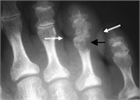

病態

1. 骨髄炎とは、細菌などが骨髄に感染したことにより起きる感染症である。血行性のほか、外傷や周囲の組織などから直接感染することがある。